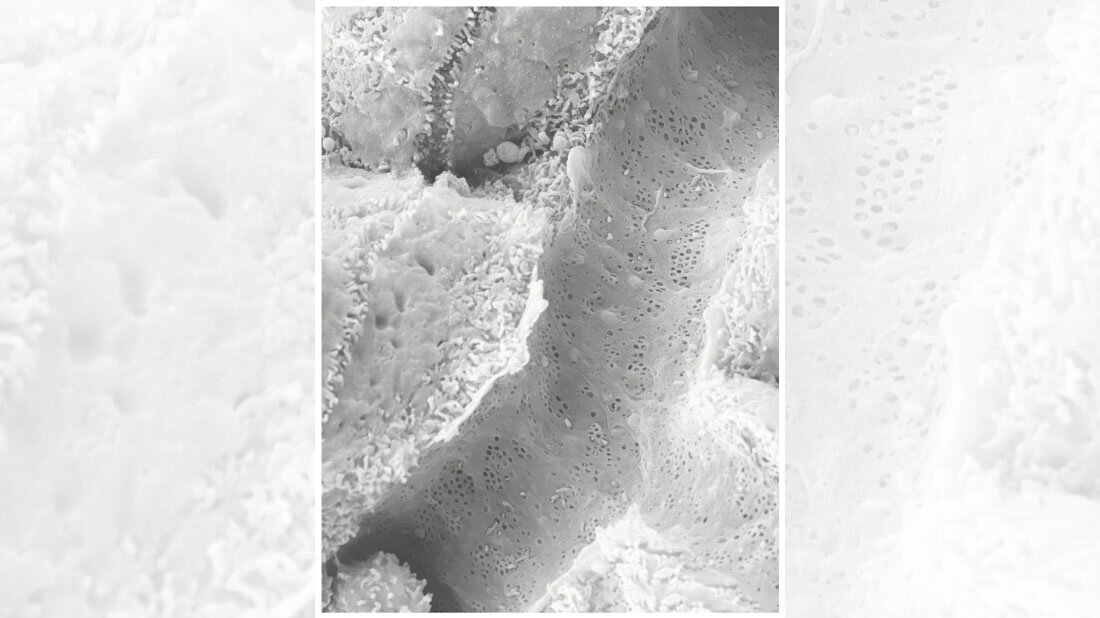

Sydney Balkenhol vom Institut für Stoffwechselphysiologie der HHU und vom DDZ, Erstautorin der Studie, weist auf eine Entdeckung des Teams hin, die mithilfe der Rasterelektronenmikroskopie gemacht wurde: „Auch in einem speziellen Mausmodell für Fettleber und Typ-2 Diabetes mellitus waren die ‚Fenster‘ in den kleinsten Blutgefäßen der Leber verschlossen.“ Dr. Daniel Eberhard, der weitere Erstautor, ergänzt: „Wir konnten den Effekt auch umkehren. Indem wir das Signalmolekül hemmten, konnten wir die Leber entfetten und so ihre Funktion wieder verbessern.“ Der Korrespondenzautor Prof. Dr. Eckhard Lammert, Leiter des Instituts für Stoffwechselphysiologie an der HHU und des Instituts für Vaskular- und Inselzellbiologie am DDZ, erhofft sich aus den Entdeckungen langfristig einen therapeutischen Ansatz auch für den Menschen: „Möglicherweise kann das von uns identifizierte Signalmolekül SEMA3A genutzt werden, um die MASLD und ihre Folgen frühzeitig zu verhindern. Doch müssen wir zunächst die Prozesse auch beim Menschen näher untersuchen.“